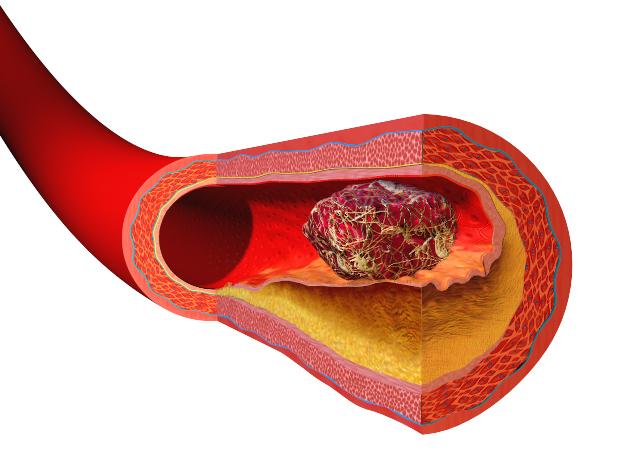

提到血栓,我們往往會感到恐懼,因為它往往跟心梗、腦梗、肺血栓等有關,而這些疾病的共同點就是可能讓人猝死。所以,對於血栓我們都要引起足夠的重視。

如果血栓源於腿部,當它形成時,靜脈中會出現腫脹,這會導緻小腿肌肉疼痛。更糟糕的是,小腿組織很厚,因此身體系統難以消除血栓。所以,如果你發現自己吃了消腫藥卻不起作用,那就說明可能存在血栓。

如果你發現身體某一處及周邊區域的溫度上升,同時該區域還會發癢或疼痛。並且,當你試圖用家庭療法治療卻失敗時,往往表明這裡存在血栓。

小腿上的深靜脈血栓,會造成嚴重的疼痛,使人步行困難並且坐著也會疼。不僅如此,腳部疼痛也是其後果之一,由於血栓妨礙血液流向足部,導致足部缺氧,造成嚴重不適。